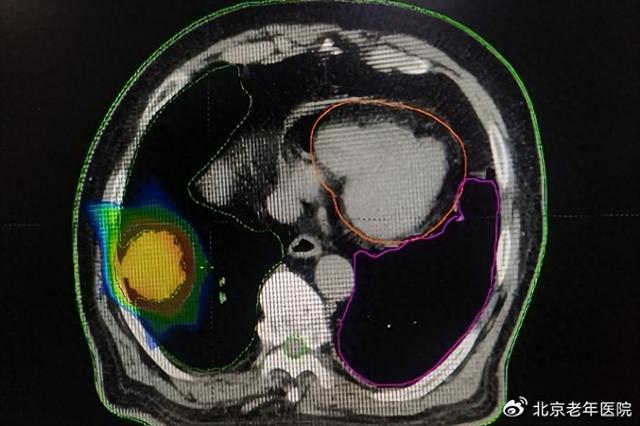

为了给李大爷提供最优的治疗,医院组织了胸外科、影像科、呼吸内科、肿瘤内科和肿瘤放疗科的多学科会诊(MDT)。经过全面评估,团队决定为患者实施局部精准放射治疗(RT),这是一种无创的局部肿瘤治疗手段,不仅能有效控制肿瘤,还可以将副作用降到最低,最大程度降低对患者基础病的影响。

从2019年4月至5月,李大爷接受了共30次精准放疗。治疗过程顺利,期间无明显不良反应。放疗团队通过实时影像引导技术,确保每次治疗都精准靶向病灶区域,力求既达到局部控制效果,又避免损伤周围正常组织。